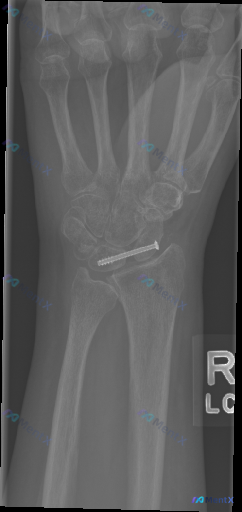

整理到一例右腕术后复查的影像资料,大家一起看看: 病例背景:成年人,右腕舟骨骨折术后复查,本次先提供右侧手腕正位X光片。 影像初步观察: - 腕部中央可见一枚内固定螺钉,横贯舟骨腰部,提示舟骨骨折手术史 - 桡骨远端、尺骨茎突及其余腕骨、掌骨基底部,未见明显新鲜骨折线或脱位征象 - 桡腕关节、下尺桡...